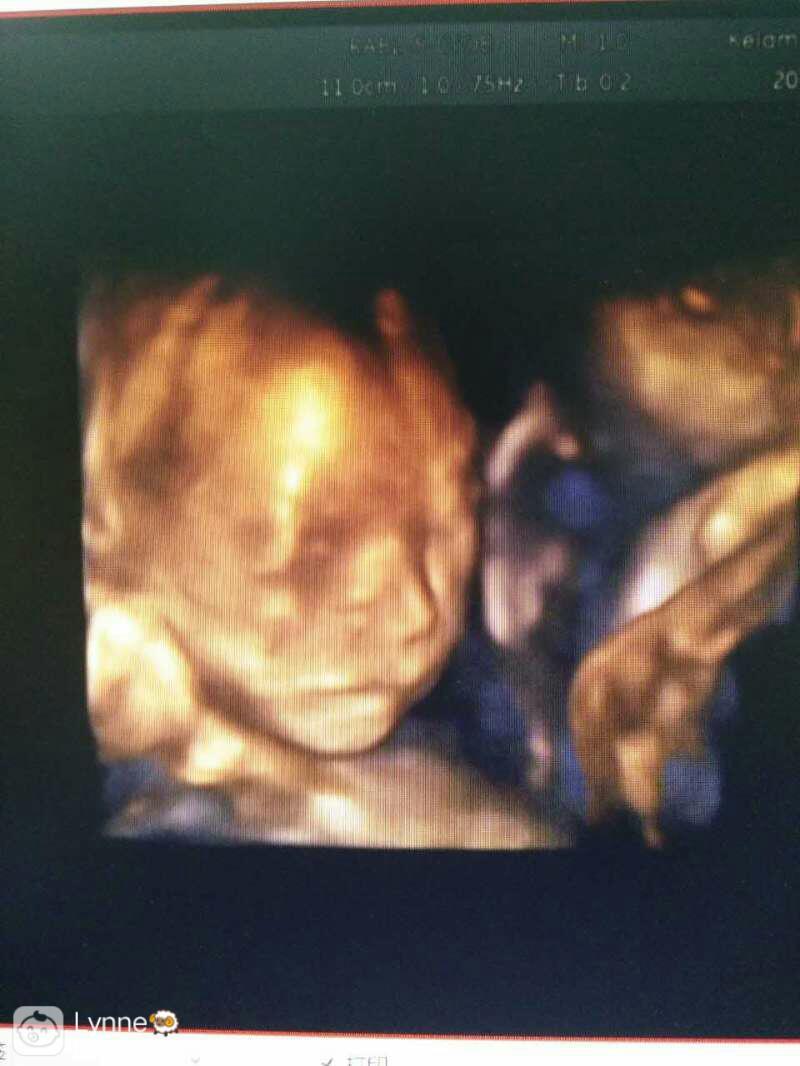

今天做的四维,各位孕妈看看,有没有看出点什么?

从抓暖图挎舞片看头部怎么患富裕有个小长角啊??

我的孕周是22+4~!!